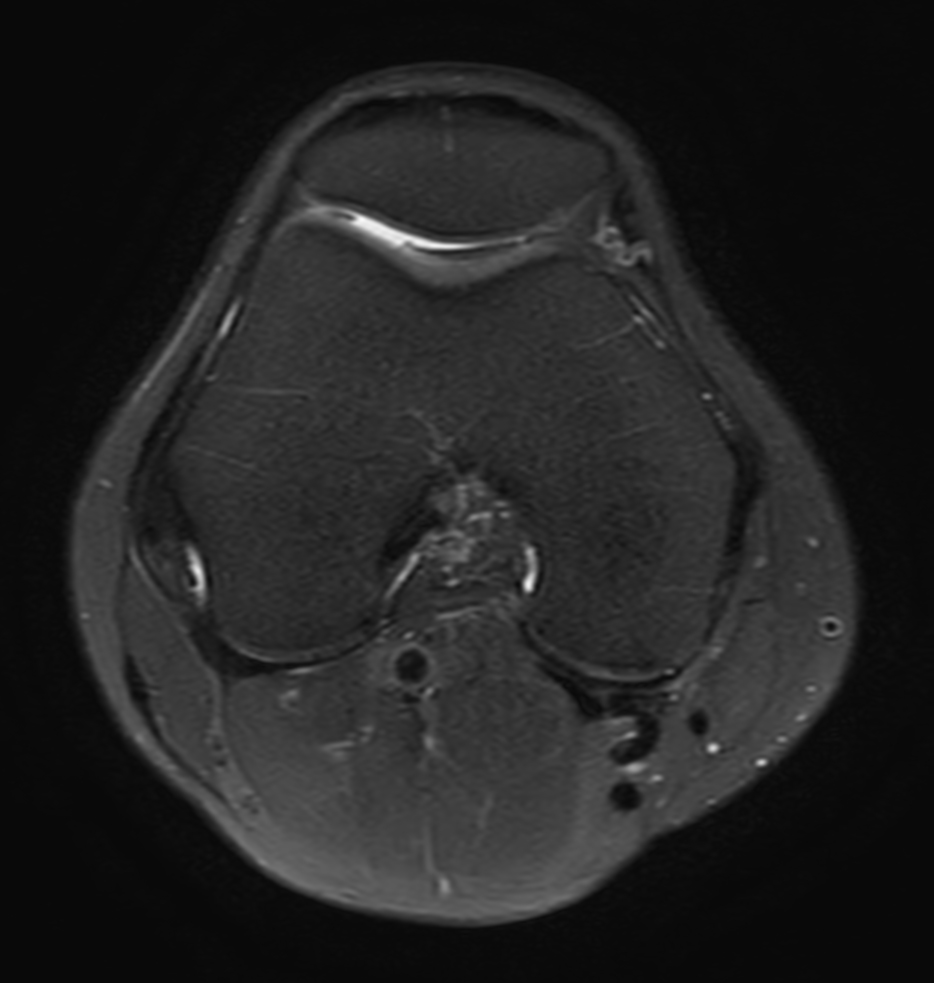

Axial PDw TSE FatSat